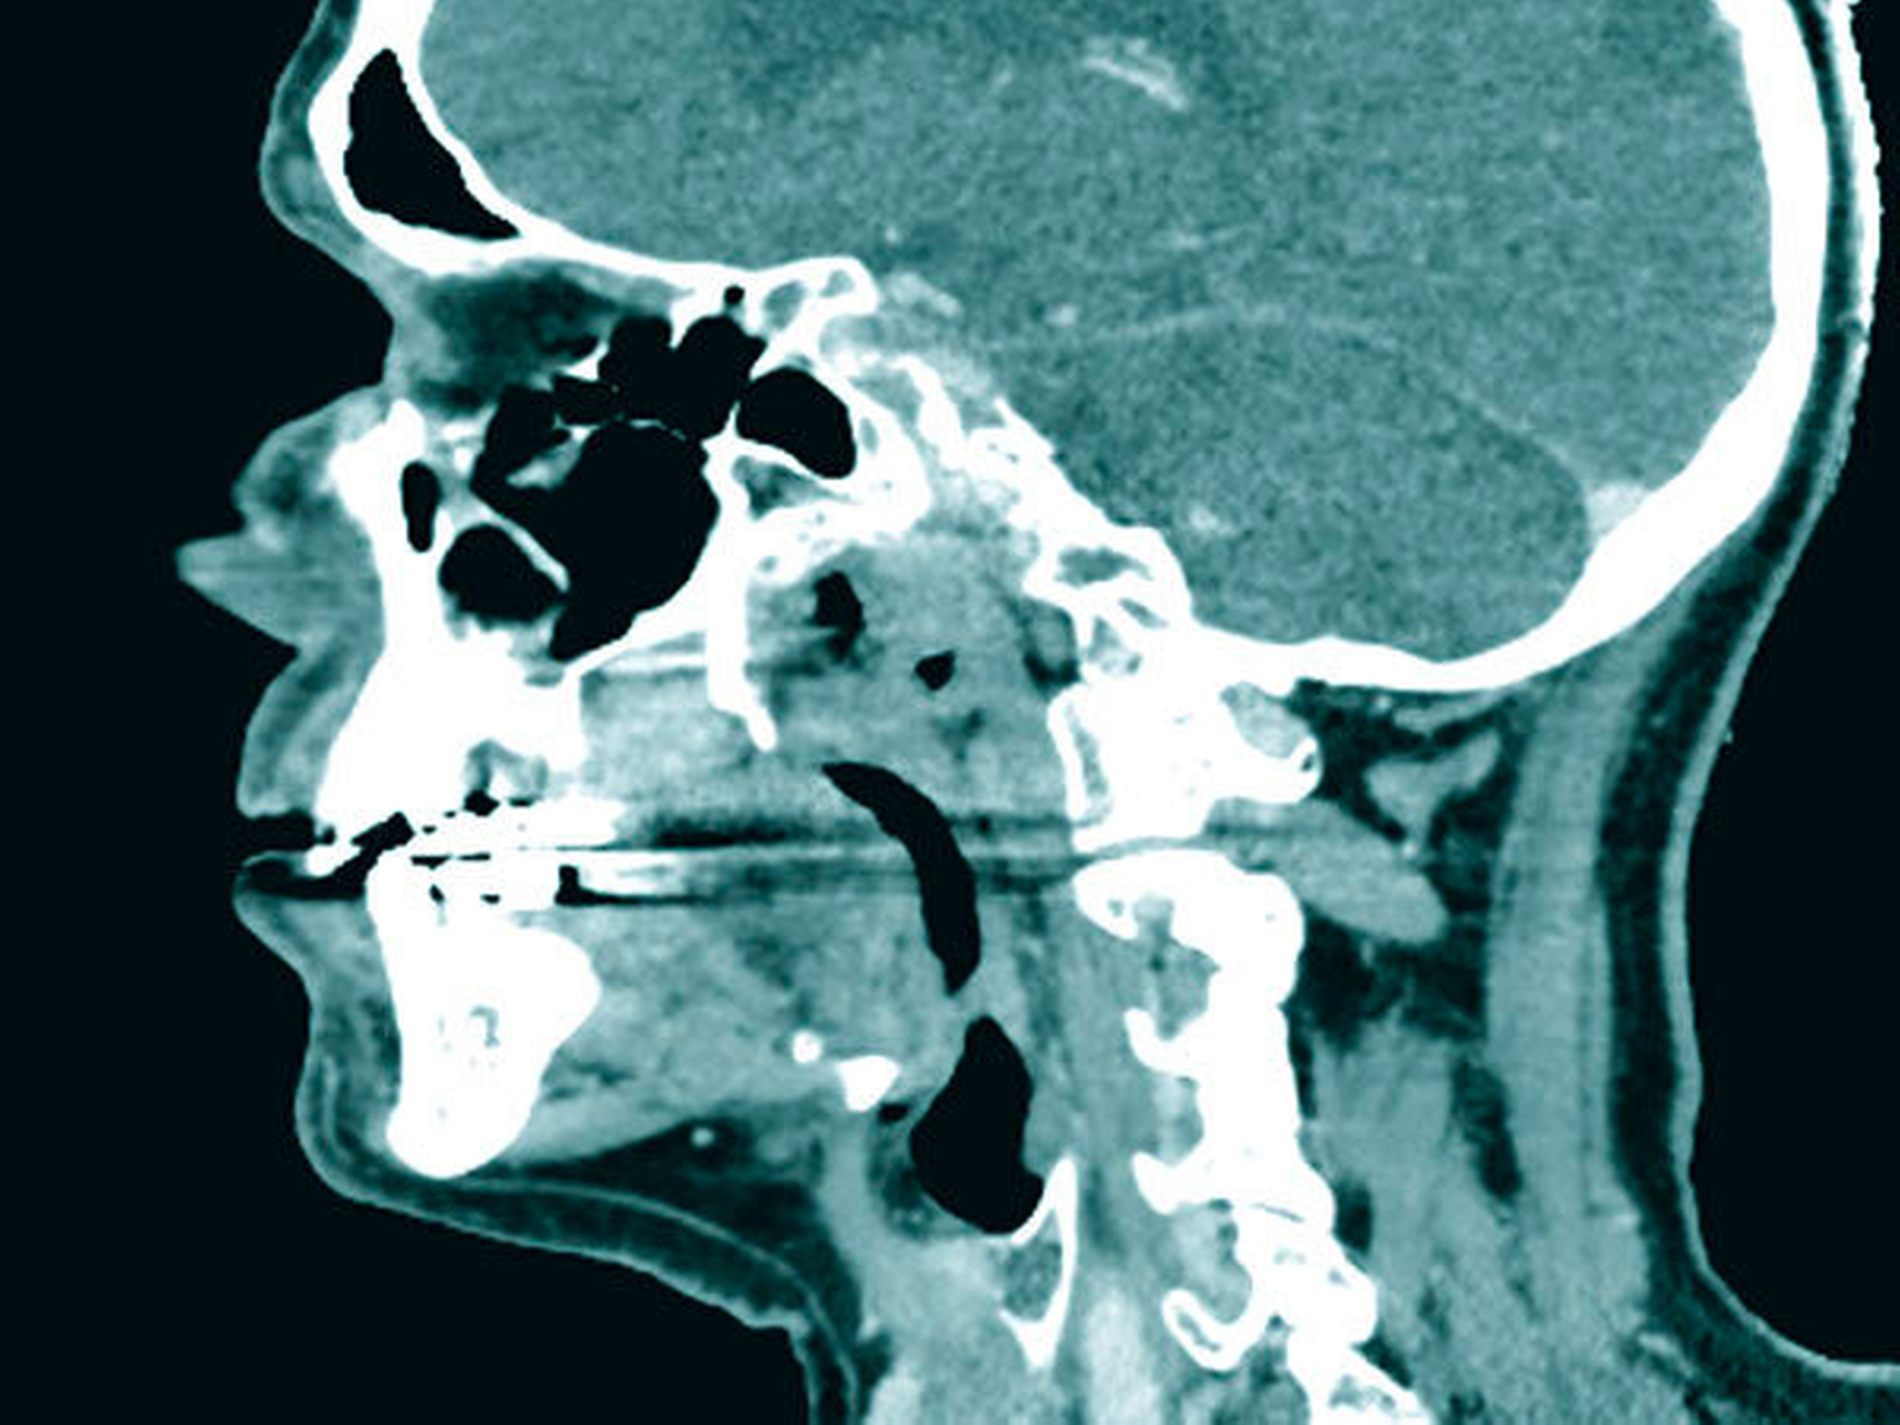

Zum Zeitpunkt der Untersuchung zeigte sich im linken Oberkiefer palatinal regio 26/27 ein livider braun-rötlicher Tumor von etwa zwei Zentimeter Größe mit Verdrängung der fixierten Gingiva nach krestal. Nach palatinal-medial war das Bindegewebe unter reizloser Schleimhaut aufgetrieben (Abbildung 1). In der Bildgebung mittels Panoramaschichtaufnahme zeigte sich in der interessierenden Region eine Verschattung der linken basalen Kieferhöhle mit Auflösung des krestalen Knochens im Molarenbereich. Des Weiteren war ein retinierter Zahn 48 und ein horizontal-vertikaler Knochenabbau bei bekannter Parodontitis zu erkennen (Abbildung 2). Zur weiteren Diagnostik wurde eine Computertomografie des Kopfes und bei Verdacht auf mögliche Metastasierung der vorbekannten Malignome eine Computertomografie des Thorax und Abdomens durchgeführt. Hierbei zeigte sich die bereits diagnostizierte Raumforderung im Bereich der linken basalen Kieferhöhle mit partieller Auflösung des molarennahen Knochens und einer weichteildichten Raumforderung im Bereich der basalen Kieferhöhle. Die kranialen Anteile der Kieferhöhle waren belüftet (Abbildung 3). Ein Anhalt für eine Metastasierung oder ein Rezidiv des Urothel- bzw. Prostatakarzinoms bestand nicht. In dem durch eine Inzisionsbiopsie in Lokalanästhesie entnommenem Gewebe zeigte sich histologisch eine teils glandulär, teils kribriform konfigurierte epitheliale Proliferation mit teils basophilem Stroma. Es lag eine deutliche Positivität für CK7 und S100 ohne Färbereaktion für CK5/6 vor. Somit entsprach der Befund dem eines kanalikulären Adenoms. Der Tumor wurde in Intubationsnarkose entfernt. Zur Kieferhöhle bestand eine dünne knöcherne Abgrenzung, die belassen wurde. Eine endoskopische Untersuchung über den mittleren Nasengang zeigte bis auf zwei kleinen Schleimretentionszysten oberhalb der Läsion – die jeweils entfernt wurden – keine weiteren Auffälligkeiten. Der Defekt wurde durch eine Einlagerung des Bichat’schen Fettkörpers und eines Mukoperiost-Lappens von vestibulär gedeckt. Die finale histologische Beurteilung bestätigte die Diagnose und eine vollständige Entfernung. Nach einem unkomplizierten postoperativen Heilungsverlauf zeigte der Patient in der klinischen Nachsorge nunmehr sechs Monate nach Operation keinen Anhalt für ein Rezidiv.

Zur Diagnostik kann entweder eine Magnetresonanztomografie oder bei knöcherner Beteiligung eine Computertomografie durchgeführt werden. Bei reinen Weichgewebstumoren der Oberlippe oder Wange kann auch eine Sonografie ausreichend sein. Das radiologische Bild entspricht einer gut abgrenzbaren Weichteilmasse mit mitunter lokal aggressivem Wachstum und knöcherner Destruktion [Smullin et al., 2004].